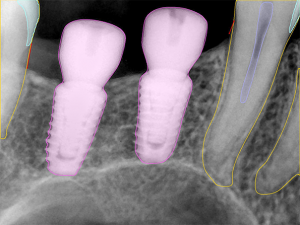

- Restoration Analysis

Identify restorative materials for treatment evaluation